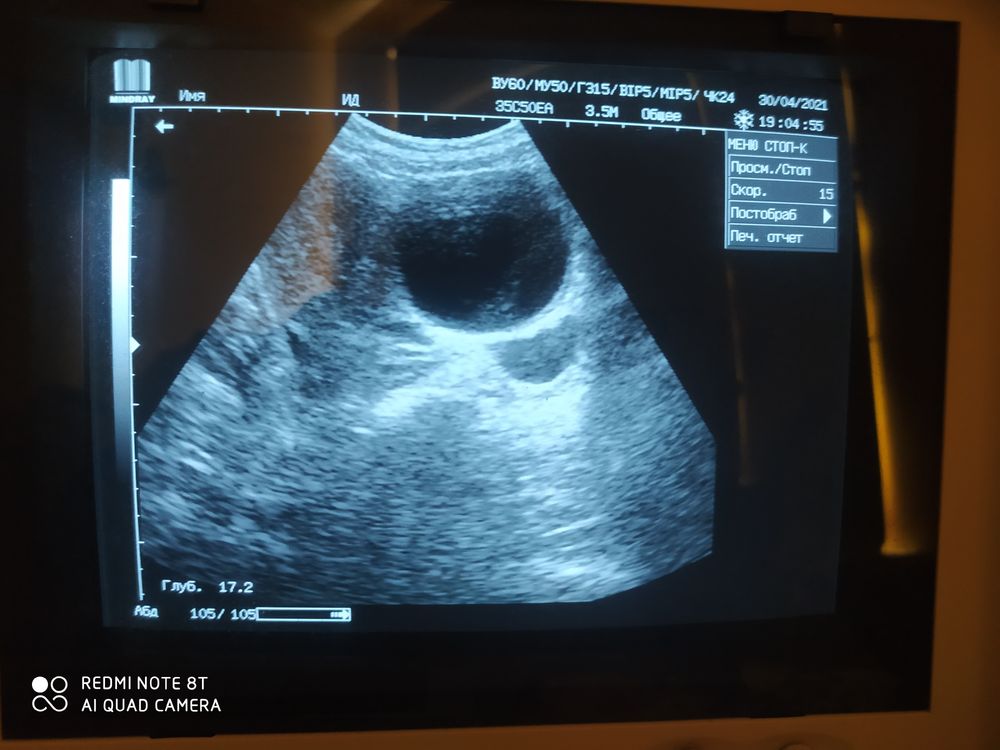

Первое фото где киста, второе фото-жидкость за маткой! Кто нибудь разбирается в этих снимках?)

Здравствуйте, задержка 5 дней, тест положительный! вчера ходила на УЗИ, врач беременность не подтвердил, но сказал в матке киста, и за маткой небольшая жидкость! Эндометрий 14,6